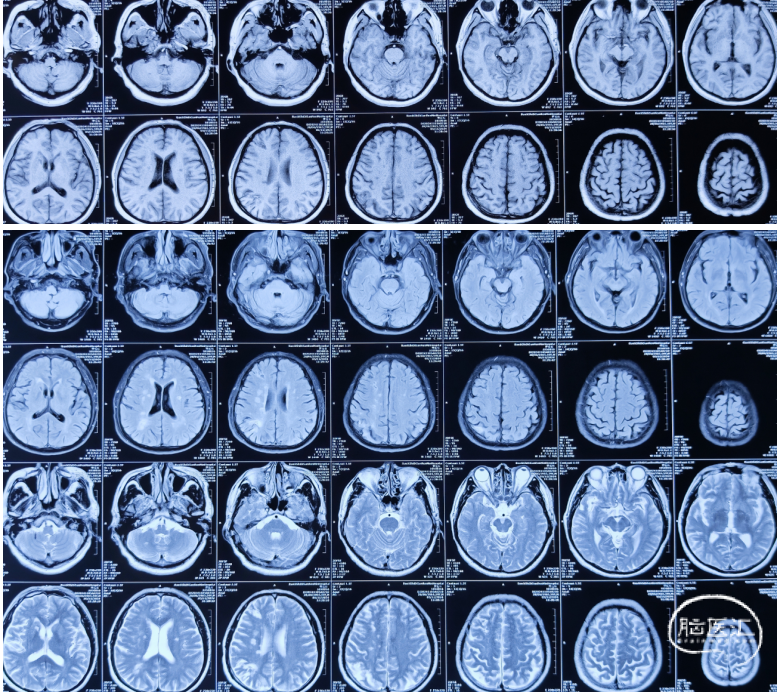

颅脑MRI+DWI+MRA(2024.11.05)

右侧放射冠多发亚急性脑梗,右侧颞叶软化灶伴周围胶质增生;多发陈旧性脑梗死;脑白质脱髓鞘改变;右侧颈内动脉闭塞,颅内动脉多发不同程度狭窄。